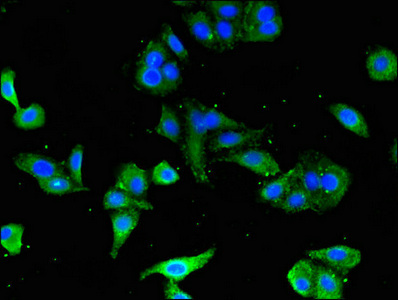

Immunofluorescent analysis of HepG2 cells using CSB-PA10499A0Rb at dilution of 1:100 and Alexa Fluor 488-congugated AffiniPure Goat Anti-Rabbit IgG(H+L)